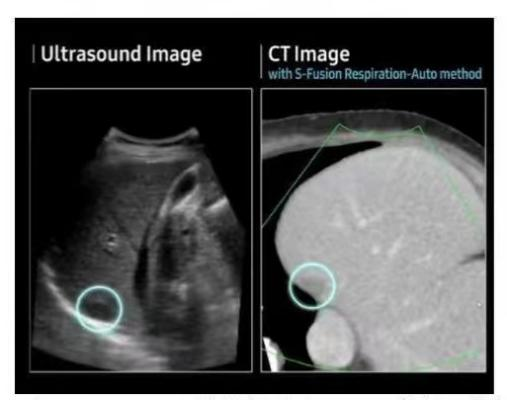

(胎儿四维成像图) (肝脏结节超声与CT对比图像)